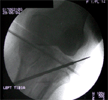

Op

Lateral Tibial Plateau Elevated and Wire inserted